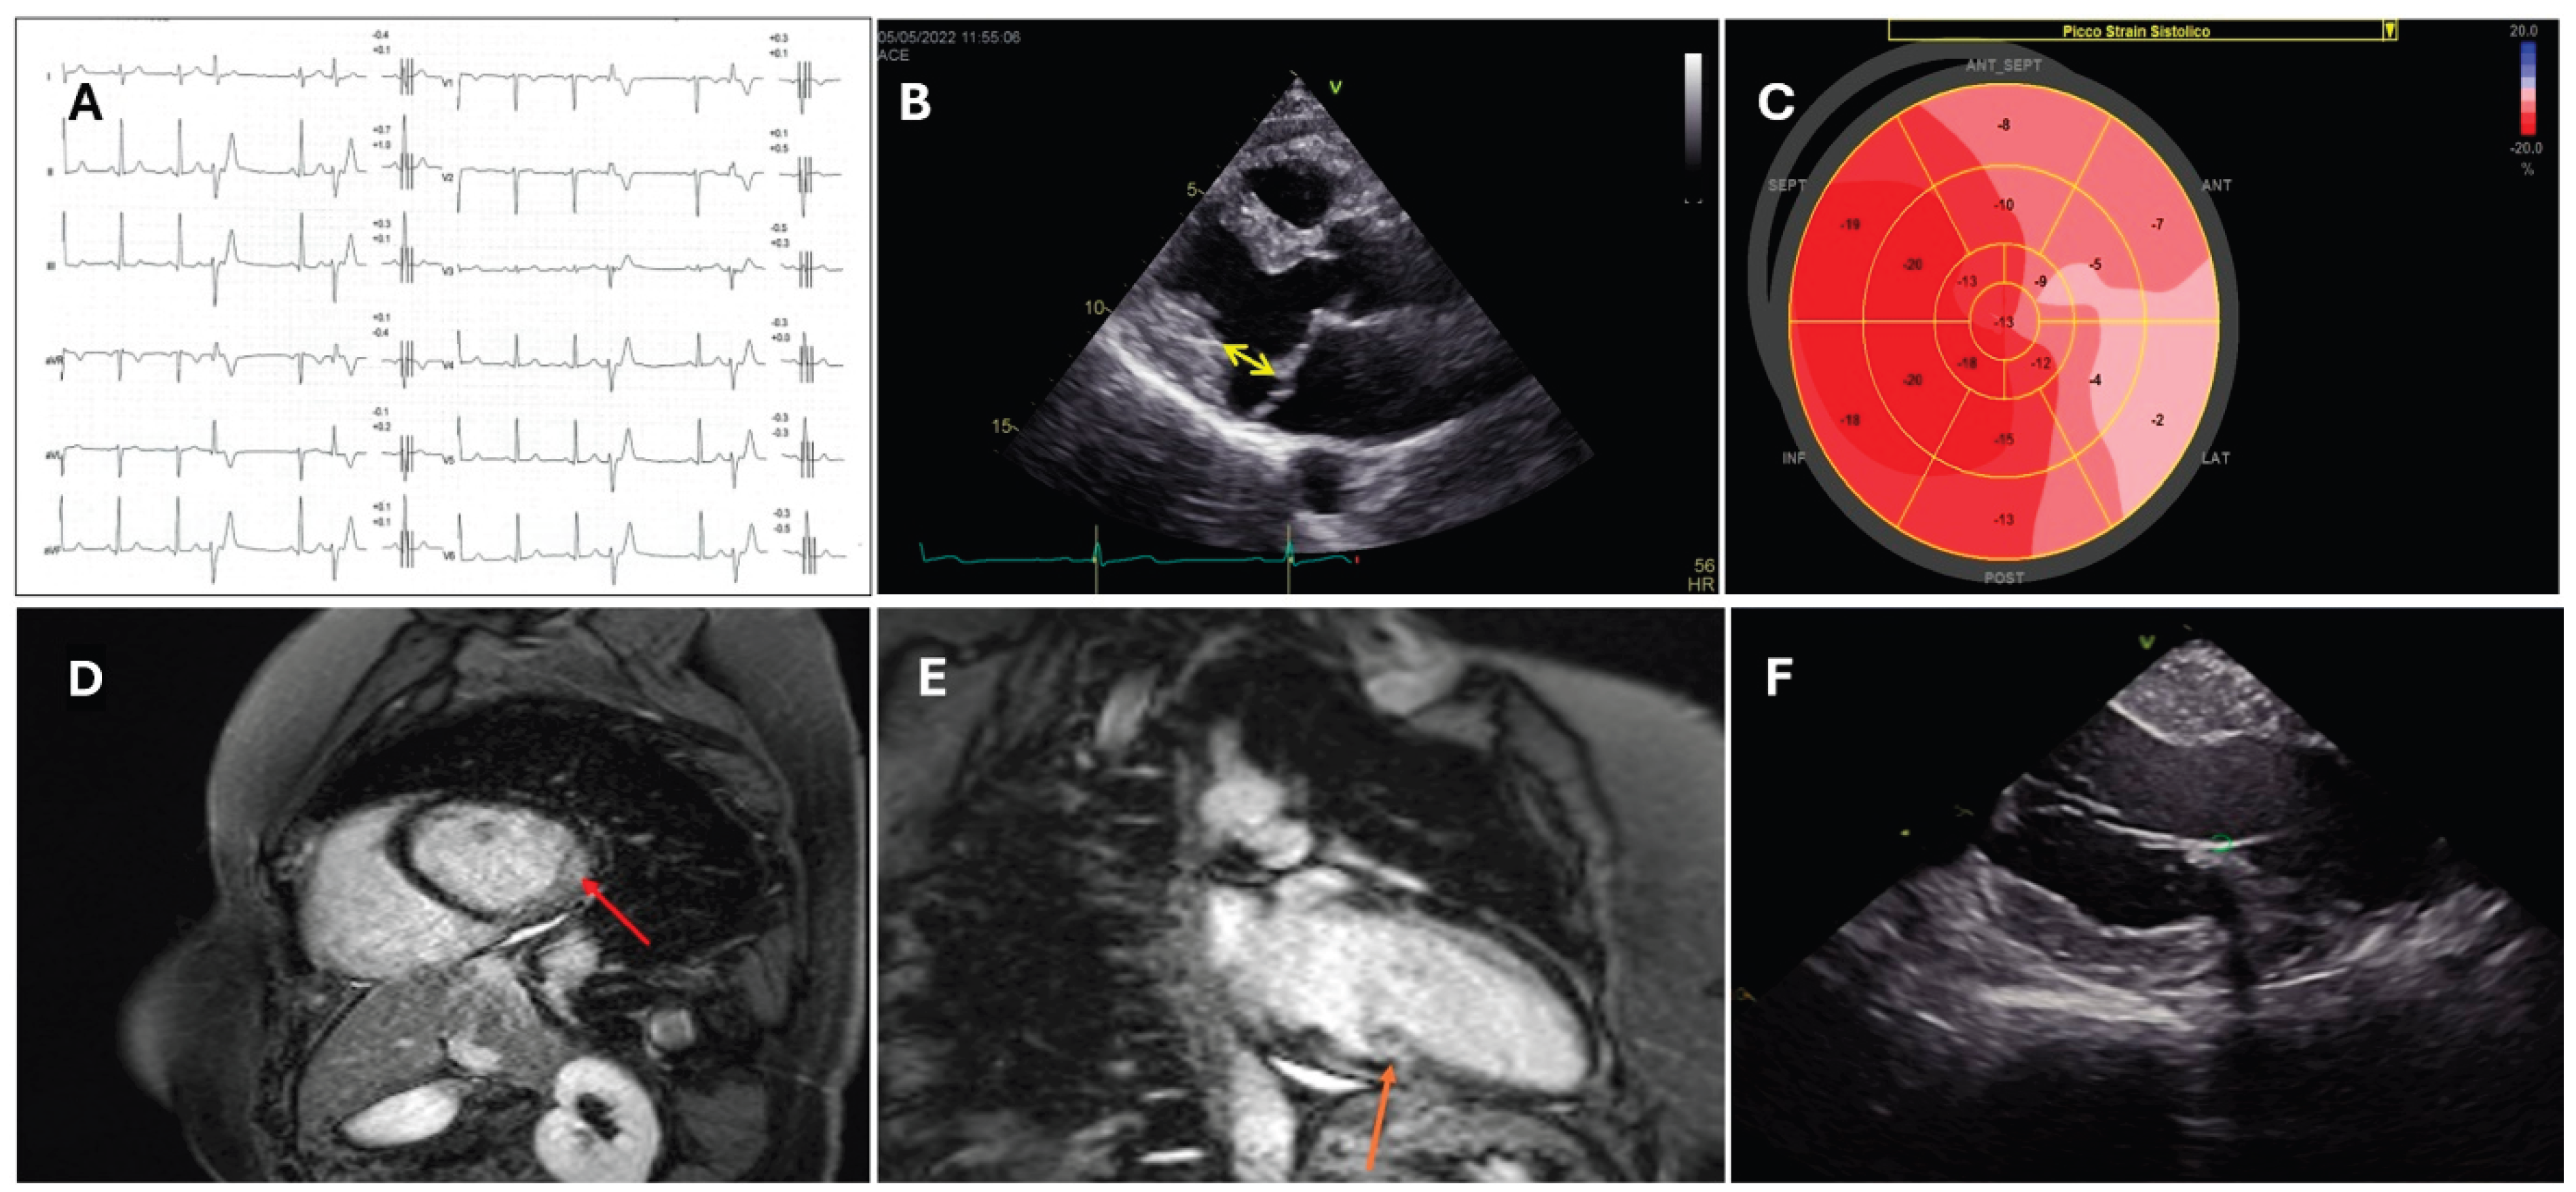

2. Pre-Procedural Imaging Assessment

3.2. Substrate Characterization